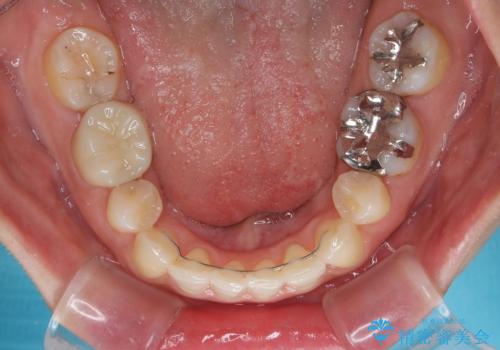

上下左右第一小臼歯4本を抜歯し、ワイヤー装置にて口元を引っ込めるよう矯正治療を行うこととしました。

奥歯が前方に傾斜していることで深く咬みこむ(ディープバイト)状態であったので、なかなか抜歯したスペースが閉じず、様々な方法でディープバイトを改善しながら治療を進めていくこととなりました。